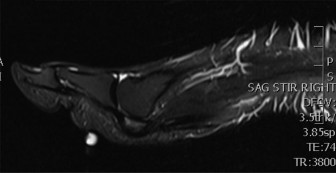

- Magnetic Resonance Imaging (MRI): The gold standard for soft tissue evaluation and often superior for bone marrow pathology.

- Medial Pain: Excellent for PTT pathology (tendinosis, tear, rupture), spring ligament injury, tarsal tunnel syndrome (nerve edema, space-occupying lesion), accessory navicular with symptomatic synchondrosis or bone marrow edema, and stress fractures of the navicular or medial cuneiform.

- Lateral Pain: Superior for peroneal tendinopathy (tendinosis, tenosynovitis, tears), subluxation (retinacular integrity), os peroneum pathology, sinus tarsi syndrome (inflammation, fibrosis), lateral ankle ligamentous injury, and stress fractures of the cuboid or metatarsals.

- Magnetic Resonance Imaging (MRI): Considered the gold standard for soft tissue evaluation and highly sensitive for bone marrow edema, occult fractures, and inflammatory processes.

- Sequences: Standard protocols include T1, T2 fat-saturated, proton density (PD), and STIR sequences in axial, sagittal, and coronal planes.

- Medial Foot Pain Imaging Insights:

- PTTD: Demonstrates tendon thickening, signal alteration (tendinosis), intrasubstance tears, or complete rupture. Fluid within the tendon sheath (tenosynovitis) is common. Associated findings include spring ligament tears, talonavicular degenerative changes, and bone marrow edema in the navicular or talar head. Staging of PTTD (Johnson and Strom) is often based on clinical and radiographic findings, but MRI helps confirm tendon integrity.

- Accessory Navicular Syndrome: Edema at the synchondrosis or within the ossicle, PTT inflammation at its insertion.

- Tarsal Tunnel Syndrome: Nerve edema, fascicular thickening, or identification of space-occupying lesions (e.g., ganglion cysts, lipomas, varicosities) compressing the posterior tibial nerve.

- Stress Fractures: Early detection of navicular or cuneiform stress fractures before radiographic changes appear, showing diffuse bone marrow edema.

- Lateral Foot Pain Imaging Insights:

- Peroneal Tendinopathy/Tears: Tendon thickening, signal changes (tendinosis), longitudinal splits, or complete tears. Tenosynovitis (fluid in the sheath) is a common accompanying feature. MRI can also assess integrity of the superior and inferior peroneal retinacula in cases of subluxation.

- Sinus Tarsi Syndrome: Inflammation, fibrosis, or synovitis within the sinus tarsi fat pad, often associated with lateral ankle instability.

- Lateral Ankle Instability: Direct visualization of ATFL, CFL tears or attenuation, chronic scarring. Evaluation for osteochondral lesions of the talus (OCLs) or impingement lesions.

- Os Peroneum Pathology: Fracture or fragmentation of the os peroneum, associated with peroneus longus pathology.

- Stress Fractures: Detection of occult stress fractures in the cuboid or fifth metatarsal.

Figure 3: An axial T2-weighted MRI scan of the ankle, demonstrating detailed soft tissue structures, including the peroneal tendons posterior to the lateral malleolus. This view is invaluable for diagnosing tendinopathy, tears, or nerve entrapment in the tarsal tunnel.